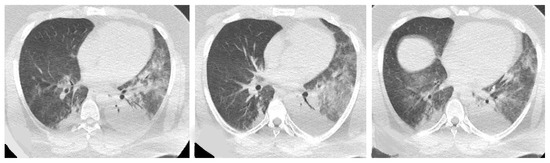

Acute Type

- Acute or rapidly progressive ILD (acute interstitial pneumonia and radiological evidence of acute respiratory distress syndrome (ARDS) due to diffuse alveolar damage) [44];